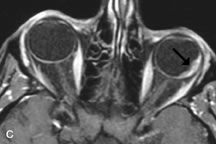

Tl relaxation time is the time required for the energized nuclei to give up the excess energy that was acquired from the RF pulse (high-energy state) and re-establish equilibrium (low-energy state) with the main magnetic field. The excess energy is released by these excited nuclei to the surrounding molecular environment, or lattice, and results in T1 relaxation, also called spin-lattice relaxation time. In different biologic tissues, hydrogen has a Tl ranging from a few hundred milliseconds to a couple of seconds. This range exists because local tissue factors affect the ability of specific protons to give up energy to the surrounding tissues. For example, hydrogen atoms attached to the carbon atoms of fat molecules relax much more rapidly than those attached to the oxygen atoms of water molecules. Viscosity, concentration, temperature, and molecular environment of the hydrogen atoms in the tissues also affect the T1 relaxation time. On a T1-weighted orbital image, fat, which has a very short T1 relaxation time, yields a high-intensity signal; the rectus muscles, which have an intermediate T1, yield an intermediate-intensity signal; and the vitreous, which has a long T1, yields a low-intensity signal (Fig. 8).5,8,16

Application of a 90° RF pulse brings the excited nuclei into phase so that the net vector of their magnetic moments is directed perpendicular to the static magnetic field. Shortly thereafter, the magnetic moments of the nuclei spread out and point in different directions, leading to a loss of phase coherence and a resultant decay in signal intensity amplitude. The T2, or spin-spin relaxation time, is the rate of decrease in the signal of these excited nuclei as a result of the interaction and transfer of energy to unexcited adjacent nuclei. T2 ranges from a few milliseconds to a few hundred milliseconds and, for a given tissue, is always less than the Tl relaxation time. T2-weighted orbital images are easily recognized by a high-intensity signal from the vitreous (Fig. 9).5,8,16